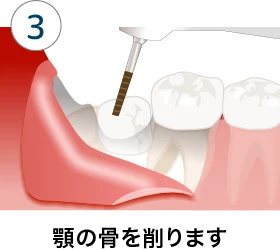

横向きや埋没している場合の抜歯方法

歯茎の切開と骨や歯の削除を行い、抜歯しますが、上顎と異なり腫れや痛みのリスクが高いです。